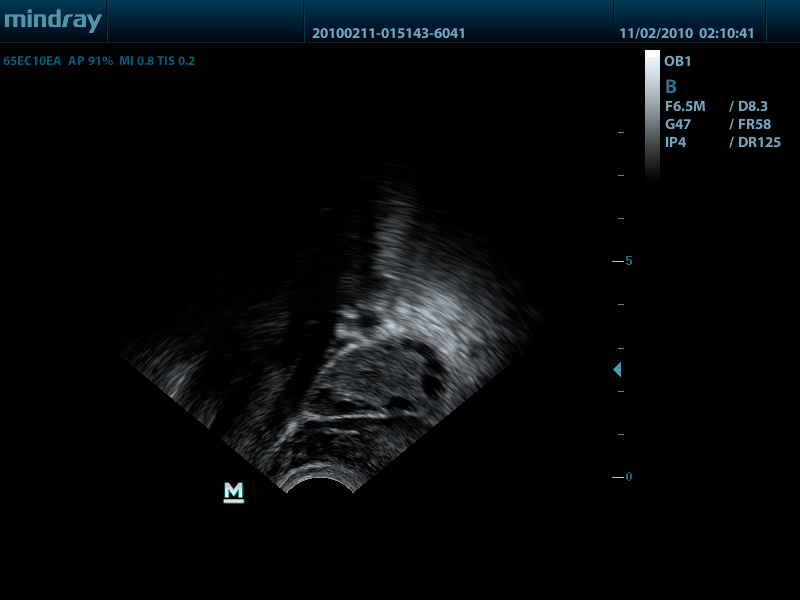

- Внутриполостной датчик 65EC10EA, 3.0 - 12.5 МГц, радиус кривизны 10 мм